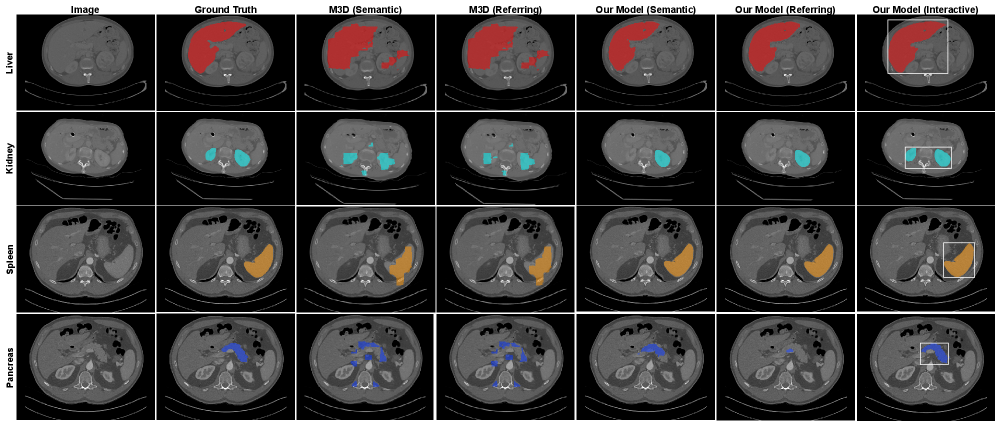

11 Qualitative Results: Segmentation Tasks

Examples of segmentation tasks on the ACT-1K dataset are presented in Figure 10. We observe that, for relatively simple cases involving large organs such as the liver and spleen, bounding box prompts provide minimal performance improvement since the results from referring and semantic segmentation are already sufficient. However, for challenging cases involving smaller or more complex structures such as the kidneys and pancreas, bounding box prompts provide additional spatial cues that significantly improve segmentation accuracy.

Refer to caption

Figure 10: Qualitative comparison of the proposed method with M3D on referring and semantic segmentation. Interactive segmentation results using bounding-box prompts are also included for comparison (ACT-1K dataset). The liver is shown in red, the kidney in cyan, the spleen in orange, and the pancreas in blue.